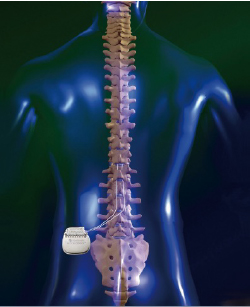

脊椎脊髄の手術 脊椎脊髄外傷 | 町田の脳神経外科・脊髄外科・神経内科「町田脳神経外科」

「脊椎脊髄の手術」平林 洌 / 長島 親男 / 戸山 芳昭 / 阿部 俊昭定価: ¥ 20000マーカー少しあり#平林洌 #平林_洌 #長島親男 #長島_親男 #戸山芳昭 #戸山_芳昭 #阿部俊昭 #阿部_俊昭 #本 #自然/医療・薬学・健康